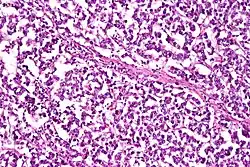

![]() |

Macrophages | Lung showing congestion with plenty of alveolar macrophages containing phagocytosed brownish granular hemosiderin pigment. | Category: Macrophages | Macrophage |